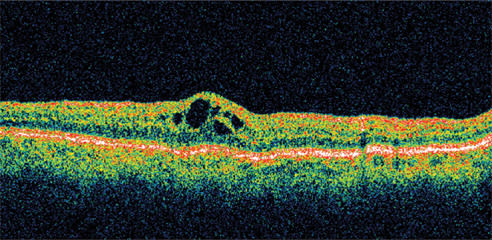

A 71-year-old man who had cataract surgery 3 months earlier was a known steroid responder with elevated IOP following surgery. At presentation, his visual acuity was 20/63. He had a fine epiretinal membrane and CME OD. Retinal thickness was 501 μm on OCT (Figure 4).

Figure 4. A 71-year-old man, who had cataract surgery 3 months earlier, presented with visual acuity of 20/63. He had a fine epiretinal membrane and CME OD. Retinal thickness was 501 μm on OCT.